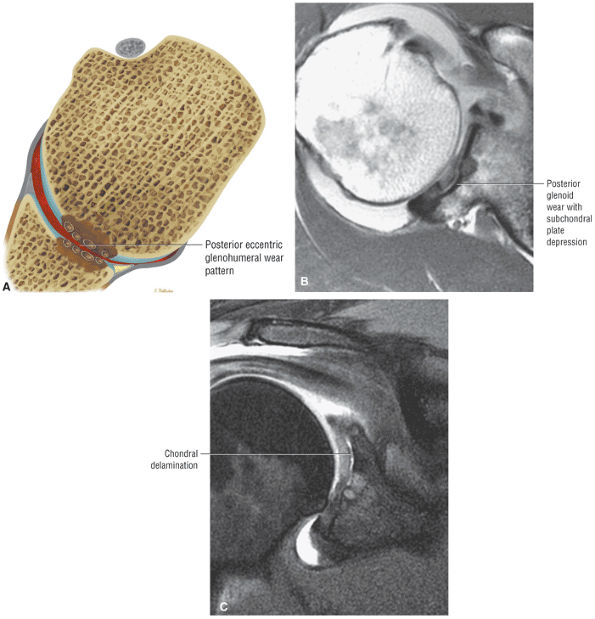

FIGURE 8.102 ● (A) The anterior undersurface of the acromion and the coracoacromial ligament form the coracoacromial arch. The subacromial subdeltoid bursa facilitates the passage of the rotator cuff and proximal humerus under the coracoacromial arch. (B) A superior axial image shows the anterior-to-posterior extent of the coracoacromial (CA) ligament perpendicular to the supraspinatus tendon. The fluid in the subacromial-subdeltoid bursa represents fluid between two serosal surfaces in contact with each other. One serosal surface is contributed by the undersurface of the coracoacromial arch and deltoid, and the other serosal surface is on the bursal side of the cuff.

|

![]() |

FIGURE 8.103 ● Pseudospur. The normal broad attachment of the coracoacromial ligament to the inferior surface of the acromion is shown on (A) T1-weighted coronal oblique and (B) sagittal oblique images. The low-signal-intensity acromial cortex (black arrows) and adjacent coracoacromial ligament and lateral slip of the deltoid attachment (white arrows) give the false impression of a small subacromial spur in the coronal plane. This pseudospur should not be misinterpreted as impingement; otherwise, unnecessary acromioplasties may be performed on patients with a normal coracoacromial ligament attachment and no associated acromial spurs.